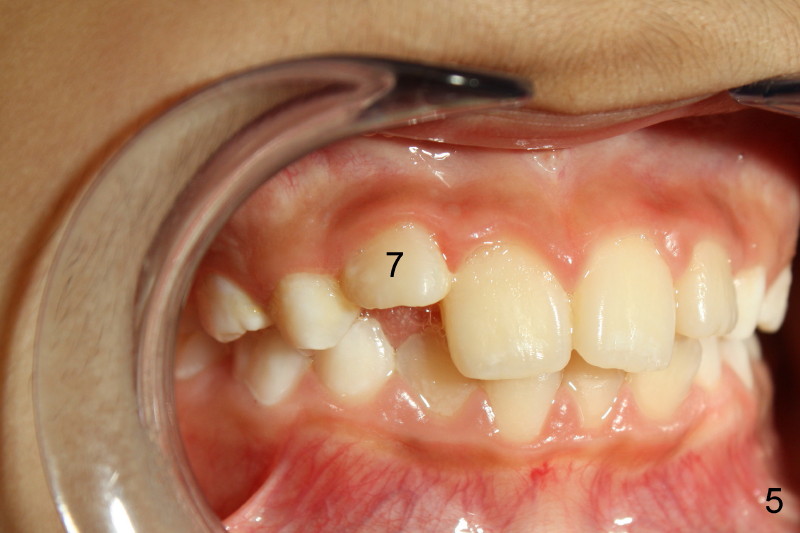

Panramic X-ray was taken when Edward was 6 years 5 months old (Fig.1). His parents and he himself found that the upper right lateral did not erupt at the age of 9 years 2 months (Fig.2-4: *). Gingivectomy was performed using soft tissue laser to expose the incisal edge of the lateral. Five months later, the lateral has erupted partially (Fig.5-8), but the family is concerned about the cosmetic issue. It appears that the upper midline has shifted to the right (Fig.6). Periapical film is planned to take to confirm the relationship between the canine and the lateral.

Appears that #7 is short a little room, therefore mechanically obstructed. Solution: make room! How? Slenderize the adjacent primary canine, extract C and H, or mild expansion. Tim Shaughnessy, DDS 11/22/2012